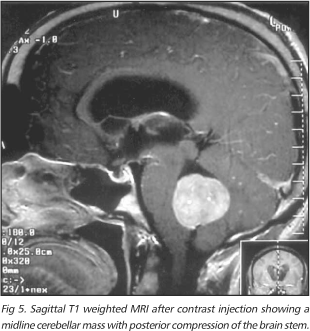

任何出现小脑肿瘤的患者都是手术的候选对象。如果患者情况稳定,可以在下一个可用的手术时间安排手术。通常手术可以等待适当的影像学研究,是脑部和脊柱核磁共振成像。矢...